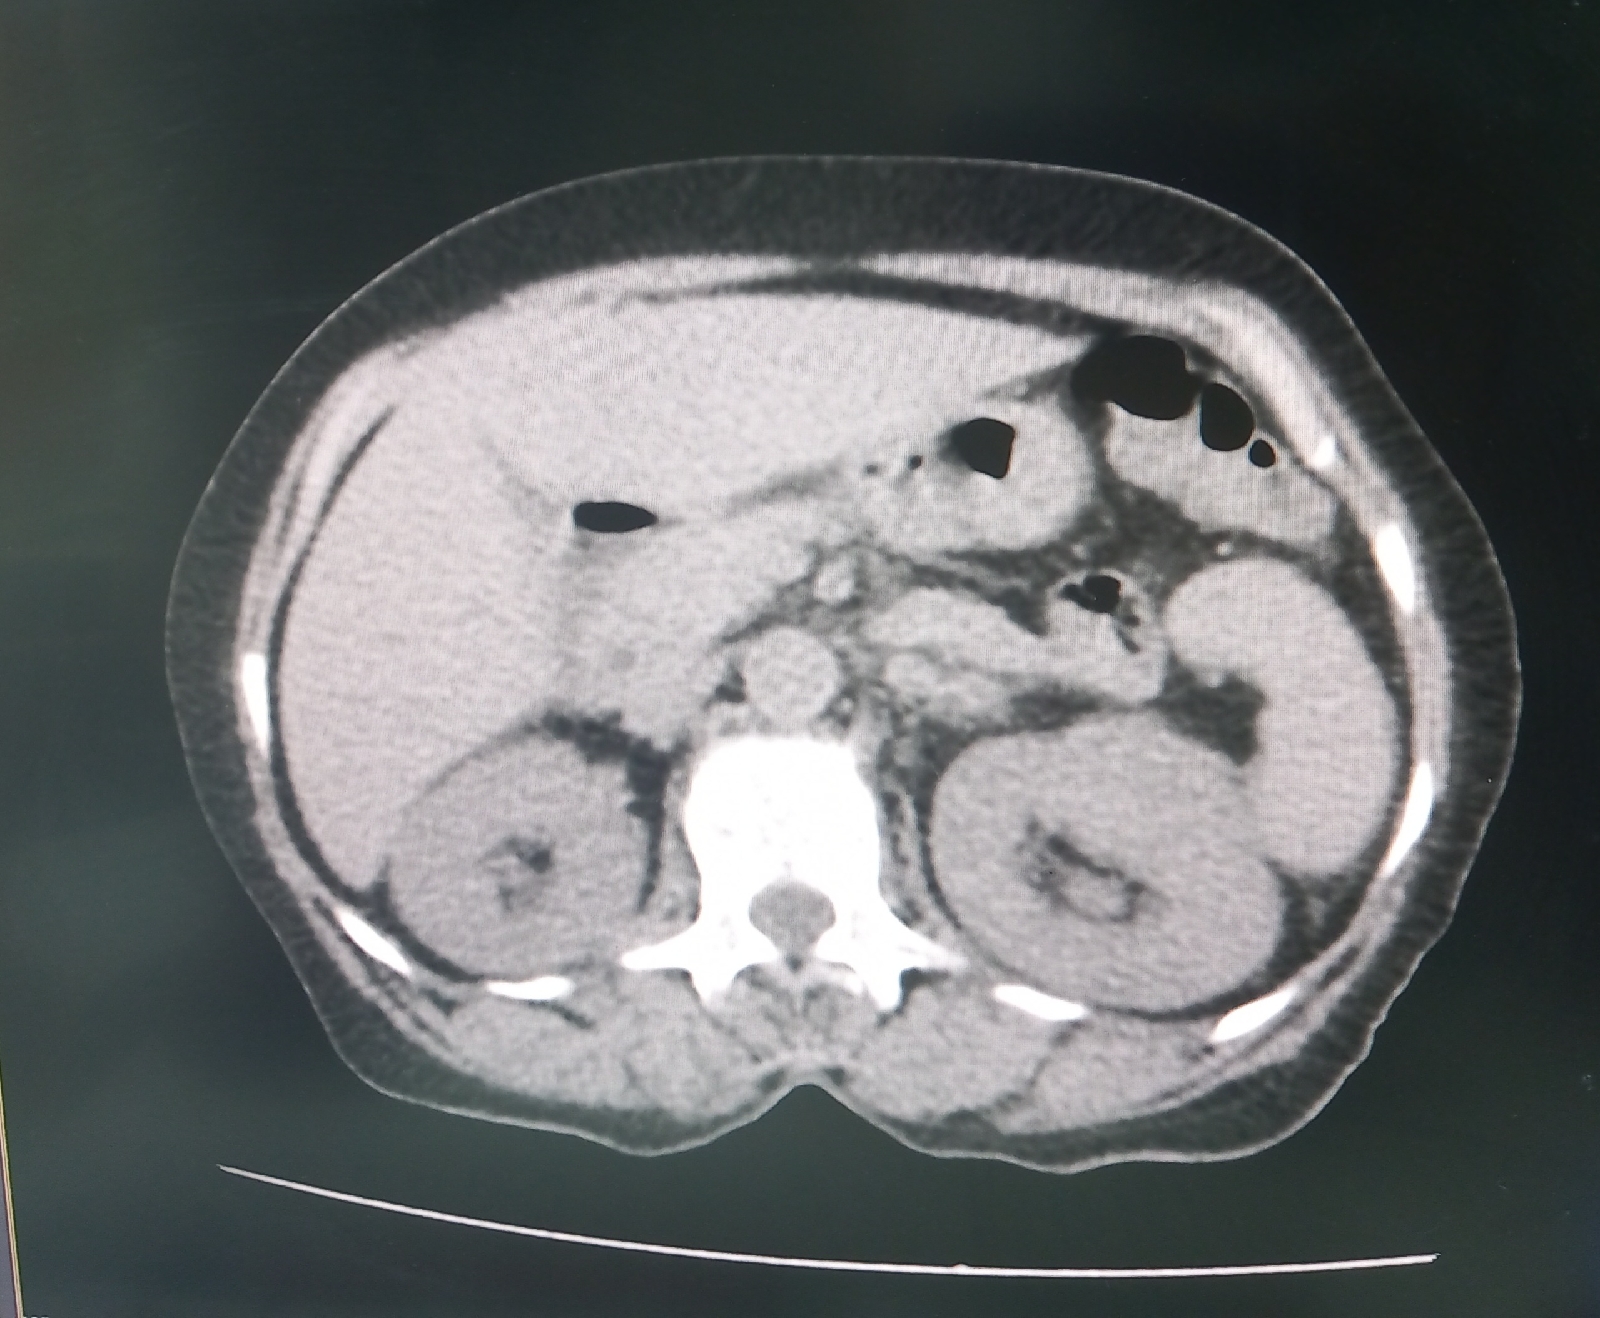

Impression-Left pyelonephritis

Diagnosis-k/C/O DM 2 with left pyelonephritis with dyselectrolemia

3.Usg

4.CT

Q.What are the radiological findings of pyelonephritis?

Usg- Altered echotexture and increased vascularity ,increase in size of kidney

CT-perinephric stranding present.,dilated collecting system.